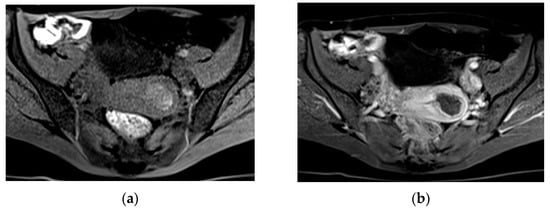

A collection of blood located anterior to the placenta between the chorionic membrane and the villous chorion and circumscribed from the umbilical cord is defined as preplacental or subamniotic hematoma (Figure 2).

Masselli et al. showed that MRI could be a useful tool for identifying PA, with high soft-tissue contrast, wide field of view, and excellent interobserver agreement [49]. The authors observed that the diffusion and T1-weighted images have higher sensitivity and diagnostic accuracy (sensitivity, 100% and 94%, respectively; diagnostic accuracy, 100% and 97%, respectively) than the T2-weighted half-Fourier RARE (sensitivity, 94%; diagnostic accuracy, 87%) and true FISP sequences (sensitivity, 79%; diagnostic accuracy 90%) in detecting hematomas. Moreover, according to changes in signal intensity of hemoglobin in placental tissue on T1 and T2WI, MRI is able to estimate the age of bleeding (Figure 3) [49].

Hyperacute hemorrhage is typically hyperintense on T2-weighted and DW images, being intermediate on T1-weighted images. Acute hemorrhage shows a drop of signal intensity on T2WI, resulting in a hyperintense T1WI. Subacute hemorrhage is hyperintense on T1WI due to the paramagnetic effect of methemoglobin. Chronic bleeding is hypointense on T1WI and T2WI. The finding of a hyperacute or acute placental hematoma should warn of the risk of progression to a higher degree of abruption, whereas subacute or late bleeding is usually stable [13,49,51]. Therefore, an accurate and timely diagnosis of PA and the prediction of its worsening are crucial when considering conservative treatment. A potentially unstable patient requires continuous monitoring and emergency preparedness. Since the diagnosis of PA is based on clinical features and not on imaging findings, MRI is not routinely performed; however, this method is extremely accurate for placental assessment, identifying the cause of second- and third-trimester uterine bleeding. MRI should therefore be considered after negative US, especially if the diagnosis of abruption could change management [13,54].